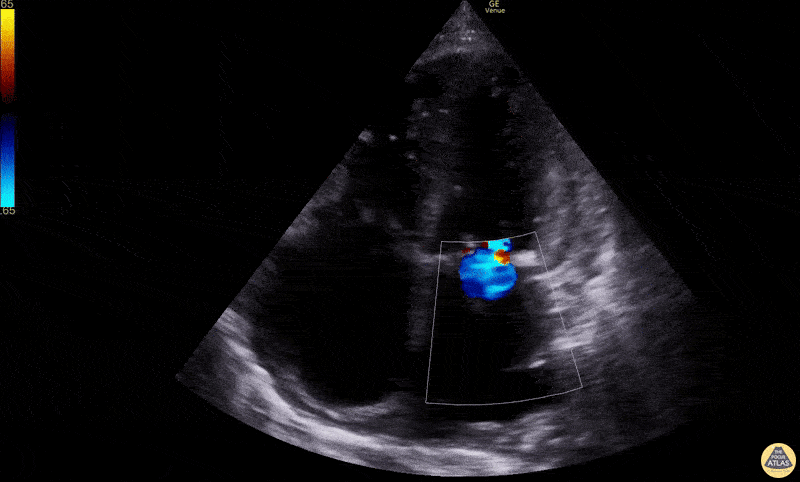

Mitral regurgitation, blue jet regurgitating into the atrium Dimitri Livshits DO, Ultrasound Fellow; Jane Belyavskaya MD, Ultrasound Fellow; Chris Hanuscin MD, Ultrasound Division Director (Kings County/SUNY Downstate)